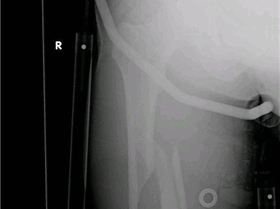

Fractured femure

Caesar